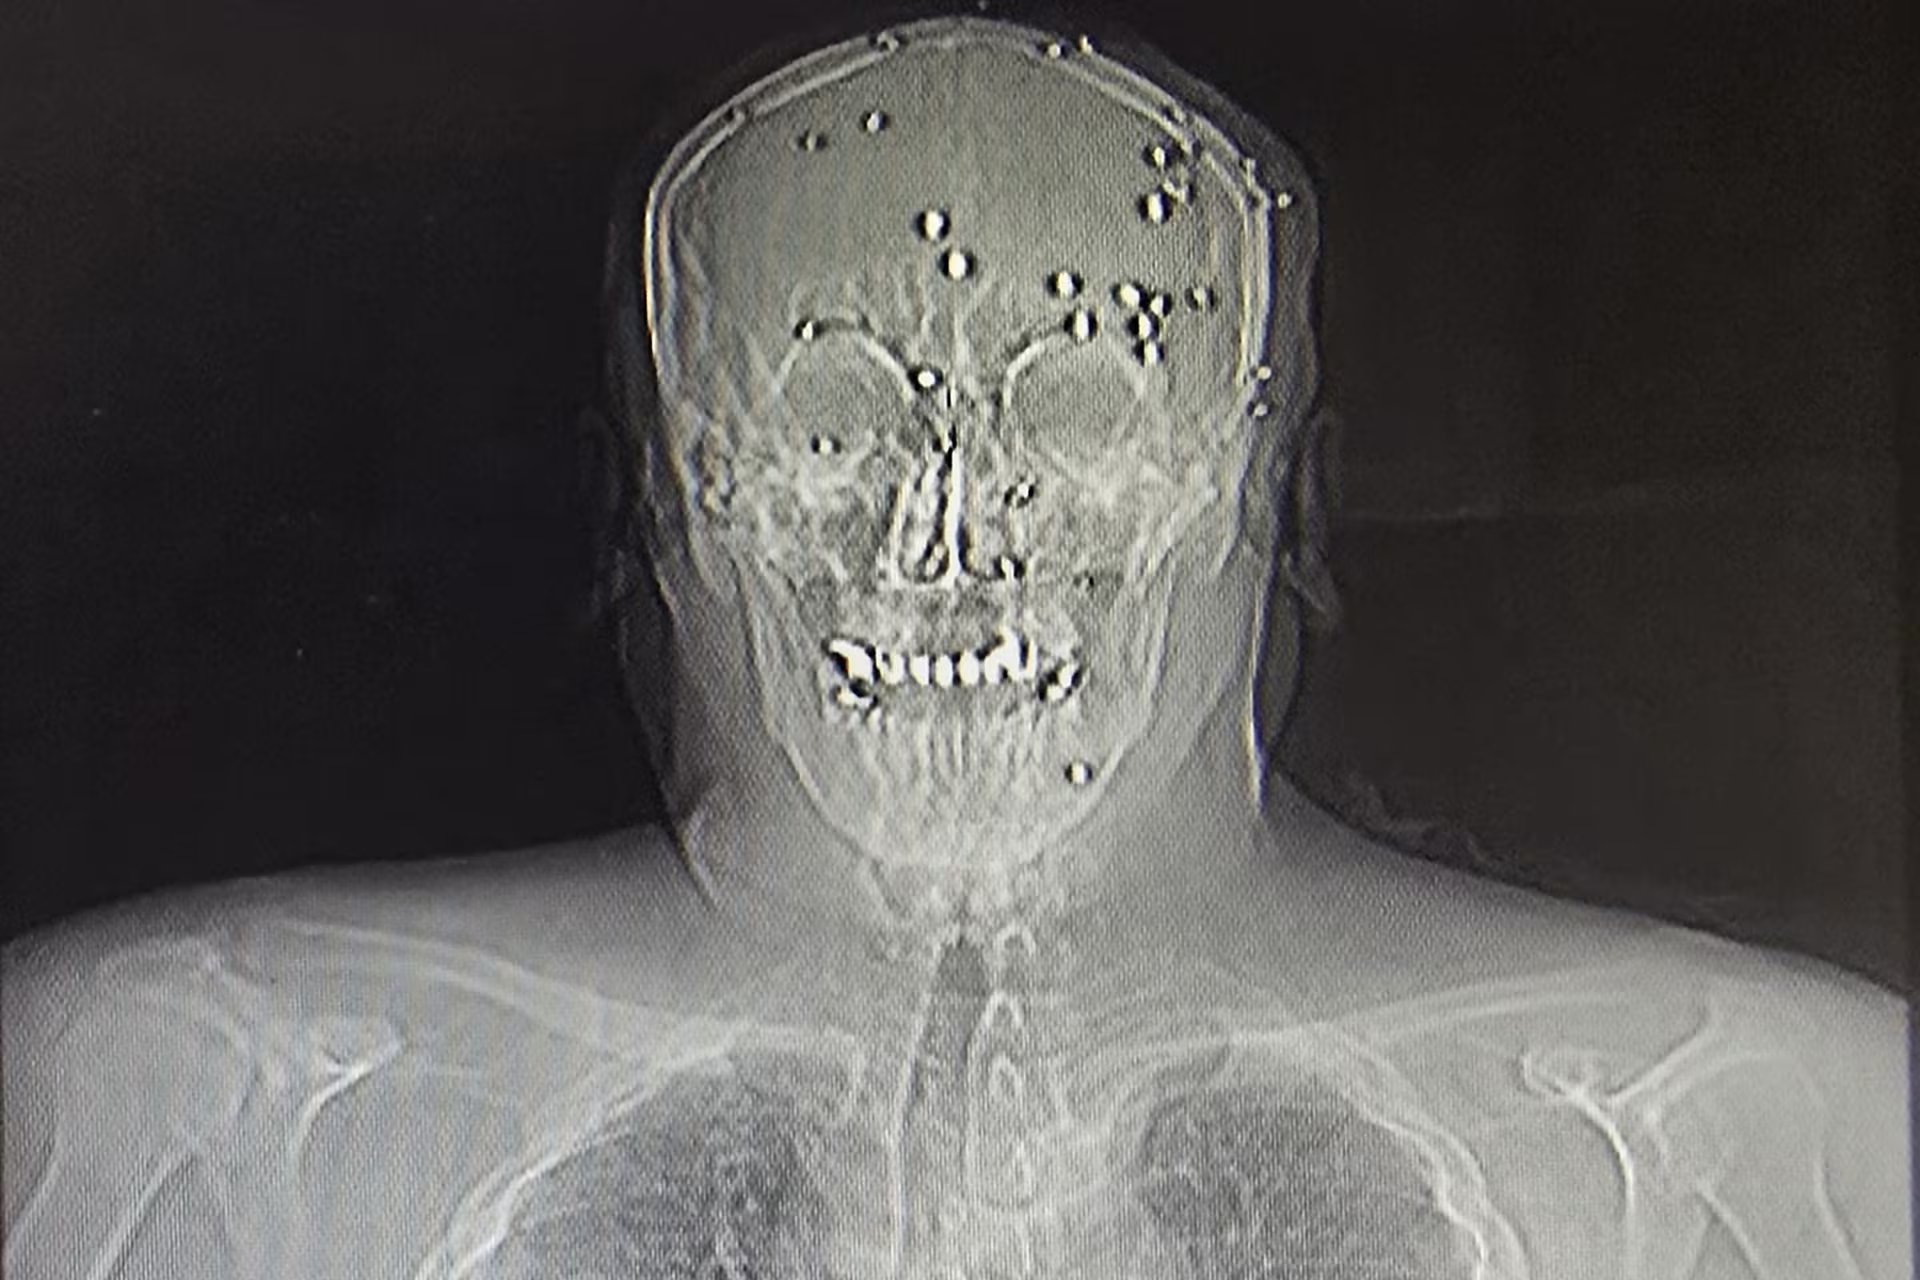

Una radiografía de una persona con varias heridas de bala (AP)